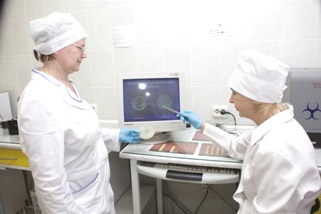

Vezetője Laboratórium Bogomolov TS és kutató Vybornova IV megvitatják a tanulmány eredményei érzékenység C. neoformans. izolált HIV-fertőzött beteg flukonazol.

Head. laboratóriumi Ph.D. TS Bogomolov tartja mikroszkópos vizsgálatok és kultúrák a patológiai anyagot gombák. Mikroszkopikus által végzett vizsgálatok fény és fluoreszcens mikroszkópia.